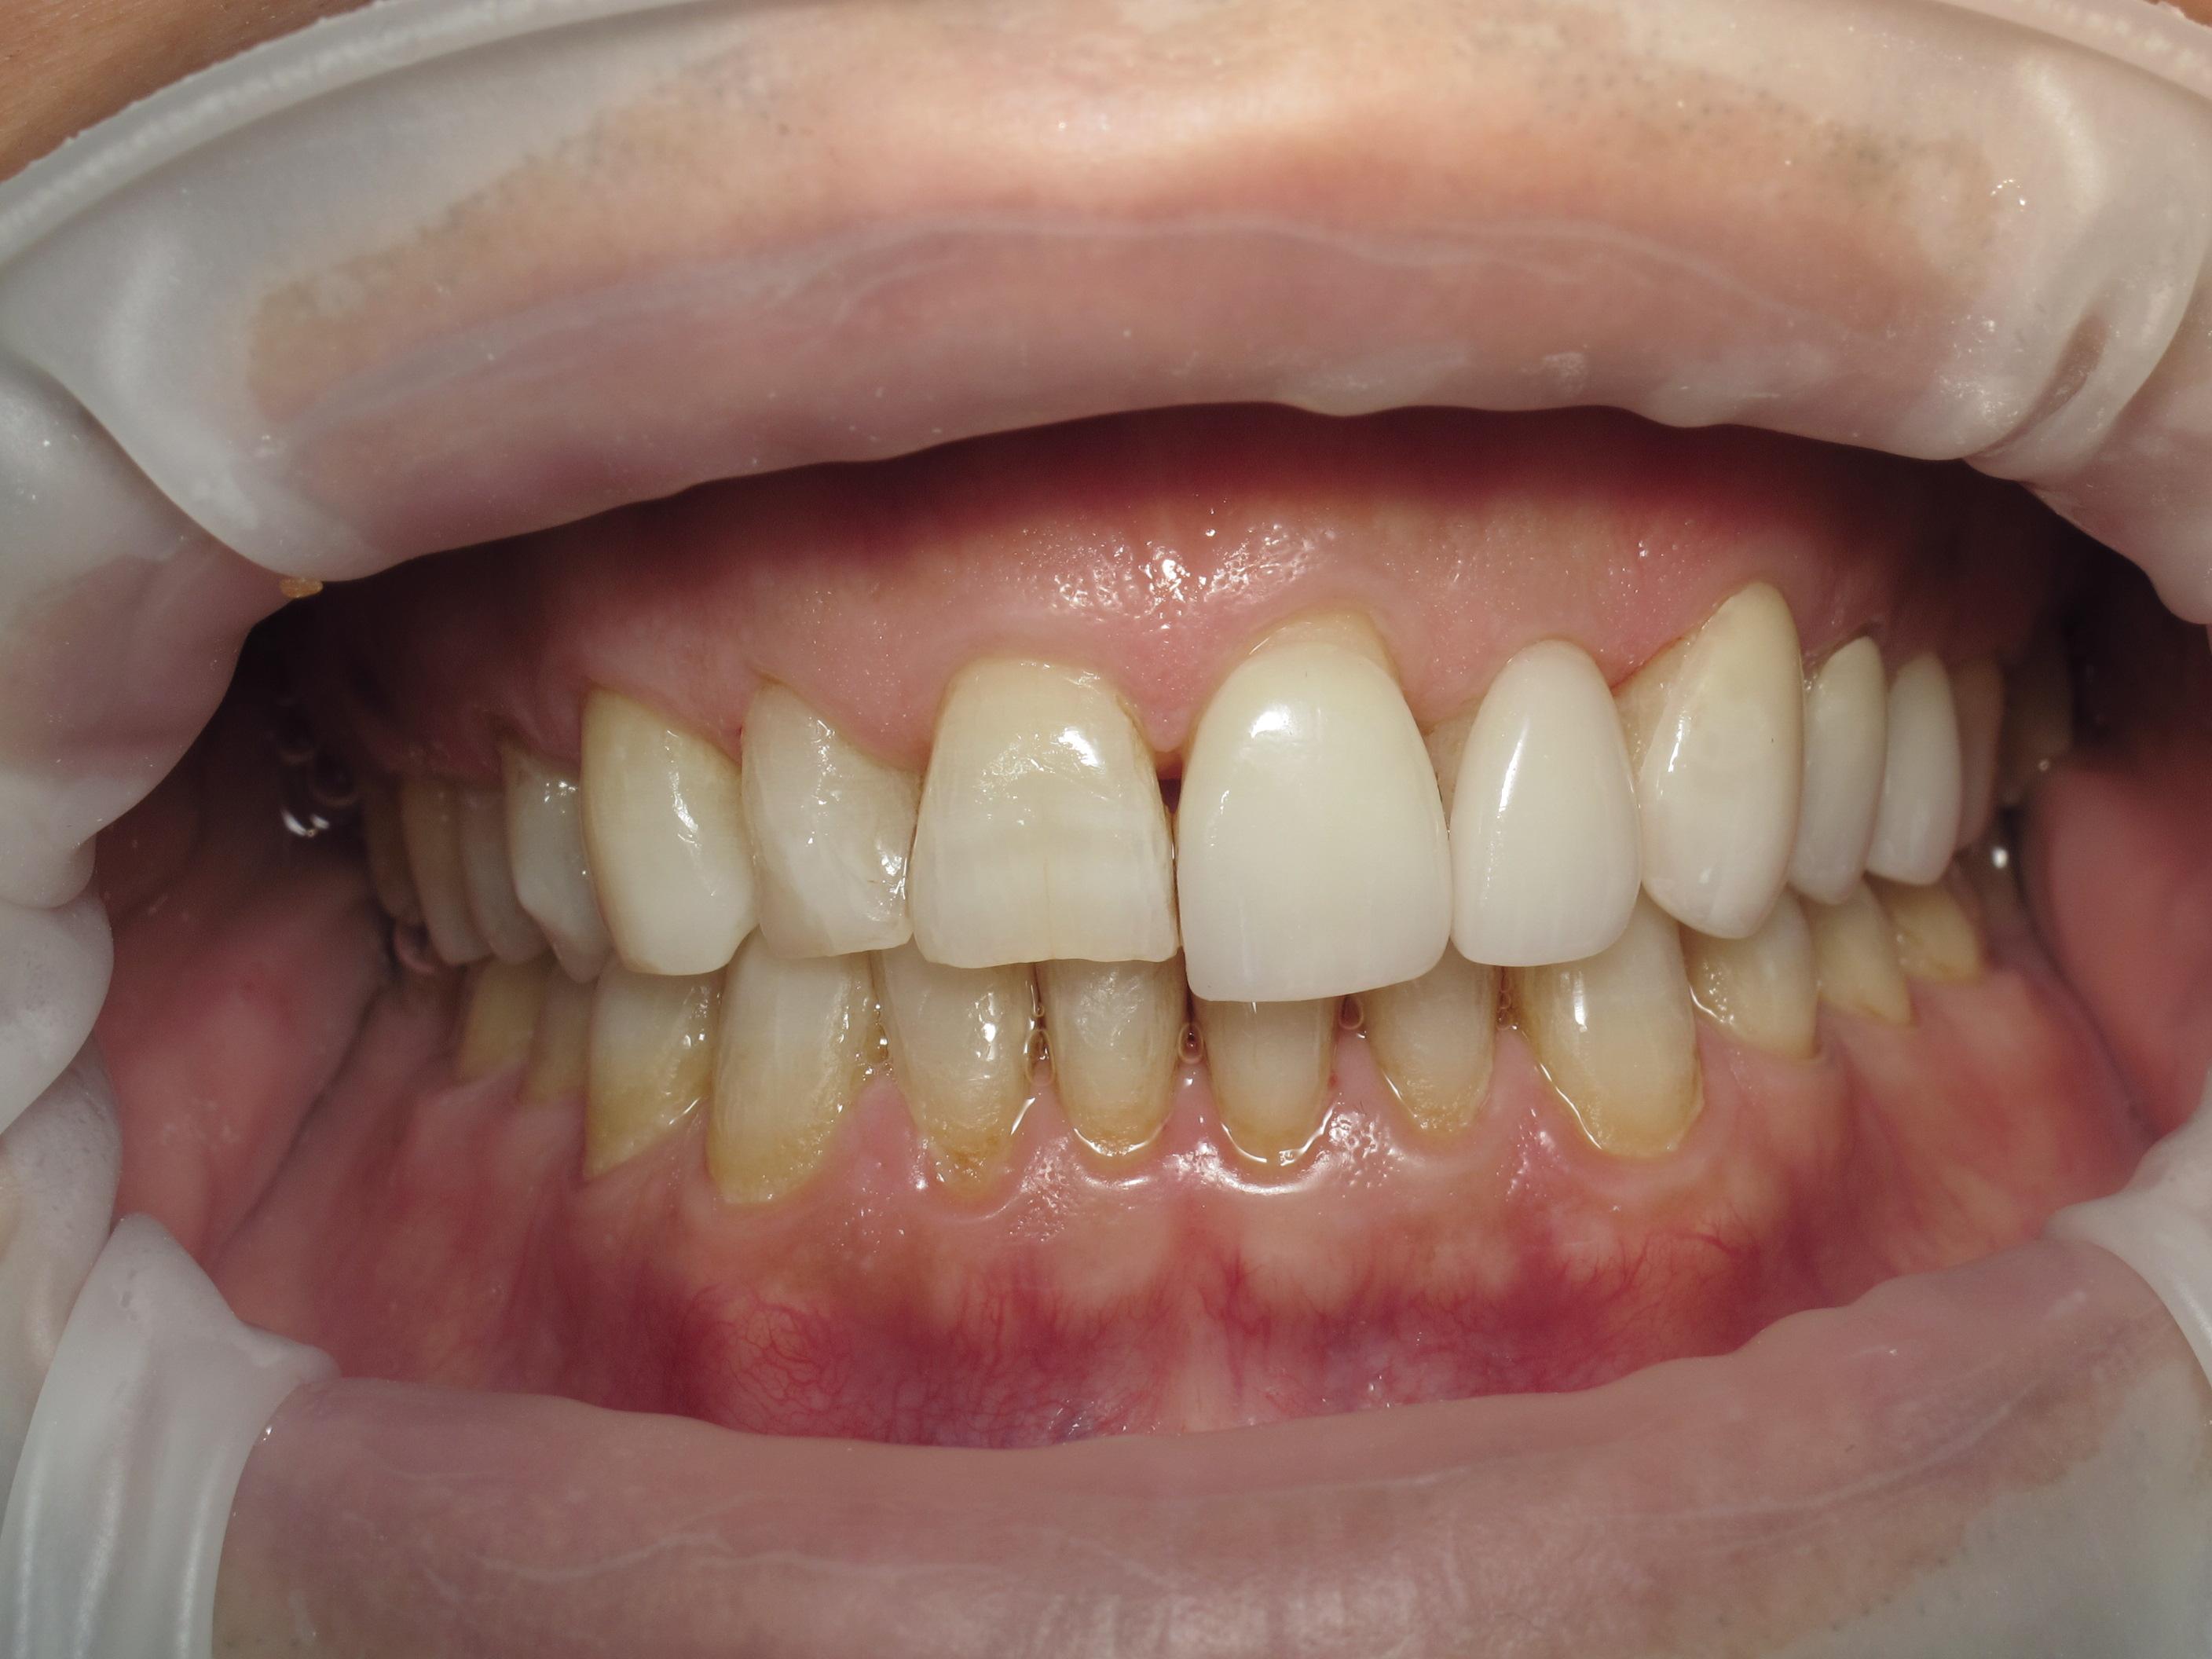

Discuss Dentistry » All Posts https://demo.discussdentistry.com/forums/forum/cosmetic-aesthetic-dentistry-2/feed/ Tue, 02 Sep 2025 00:41:25 +0000 https://bbpress.org/?v=2.6.11 en-US https://demo.discussdentistry.com/forums/topic/orthodontic-treatement-or-smile-redesigning/#post-26156 <![CDATA[Orthodontic treatement or smile redesigning]]> https://demo.discussdentistry.com/forums/topic/orthodontic-treatement-or-smile-redesigning/#post-26156 Mon, 12 Aug 2024 10:08:02 +0000 site_admin Dear all eminent orthodontists, Help required with this case.Female patient /Age…44 yrs / No relevant medical history

Patient came with a complaint of upper right central incisor drifting and  ” slightly coming outside.”  and it seems lower anteriors  have also tilted labially a little. This perhaps is due to gum recession and tartar accumulation.. The images shown below are after scaling.

What is the treatment?

Will orthodontic treatment work?  If yes can this case be done with aligners?

The local aligner company has suggested IPR of lower incisors and thereafter retroclination of U/L incisors. Is this possible or should I treatr the case with smile redesigning. The patient also wants other diastemas to be closed.  Hope to see a lot of responses and many thanks in advance for the same.

Frontal View20240808_205936SANDHYA NAIR LATERAL CEPHALOGRAM 2.8.24_01_01Lower after scalingSANDHYA NAIR OPG 2.8.24_01